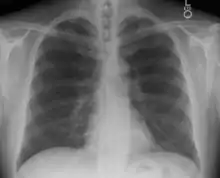

Refer to e.g. the quality of the images produced by each method (resolution, contrast...), as well as possible dangers.

Example images are useful to help you to explain why one technique is better than another. |